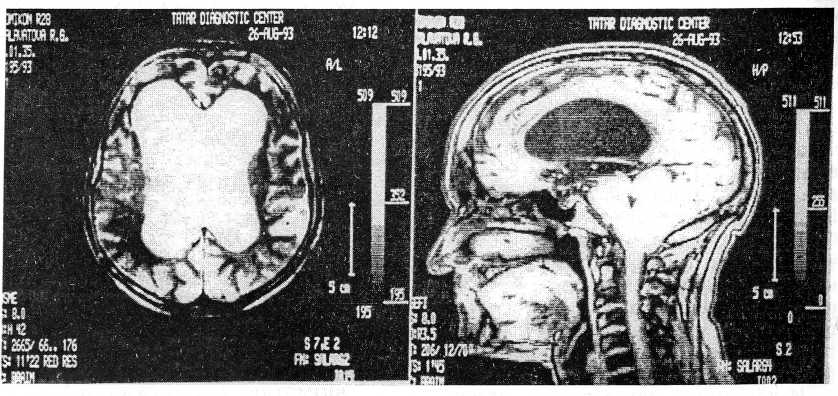

Сроки от начала заболевания до поступления пациентов в стационар колебались от 0,5 года до 14 лет. Наиболее короткий анамнез заболевания имел

Место у пациентов 10—20 лет, у которых в клинической картине доминировал гипертензионно-гидроцефальный синдром в связи с аномалией Арнольда—Киари (рис. 1).

Рис. 1 Гидроцефалия и аномалия Арнольда—Киари (МРТ).